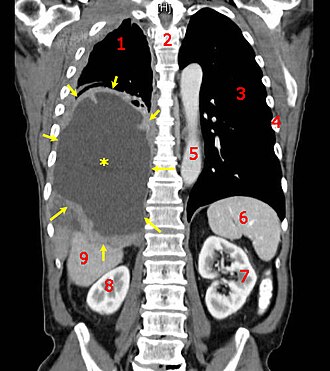

Diagnosis relies on histopathology, molecular profiling, and imaging modalities refined by collaborations among Radiology departments at places like Mayo Clinic and pathology laboratories at Memorial Sloan Kettering Cancer Center. Staging systems such as the TNM classification and disease-specific schemes published with input from organizations like the American Joint Committee on Cancer guide prognosis. Biomarker discovery owes much to consortia including the Cancer Genome Atlas and translational programs at Wellcome Trust Sanger Institute.